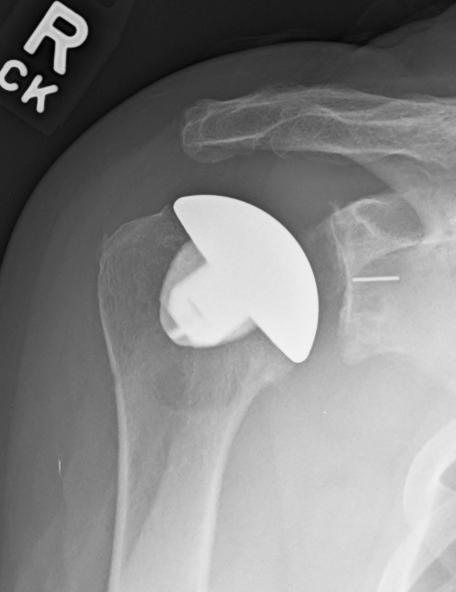

By Yuri Lewicky, M.D.

The human body has an incredible ability to heal. Yet, with age, repetitive use or injury, that healing capacity has limits. While avoiding surgery is always preferable, modern shoulder medicine offers excellent solutions when surgery becomes necessary.

WHEN SHOULDER REPLACEMENT

SURGERY IS THE BEST OPTION

Surgery may be the right choice when pain and stiffness persist despite therapy and medication. There’s no need to suffer. Shoulder replacement has advanced dramatically, offering implants tailored to each patient and condition. Outcomes are better than ever.

TWO SURGICAL OPTIONS

There are two surgical options for shoulder arthritis: Partial shoulder replacement (hemiarthroplasty) and total shoulder replacement (anatomic).

The goal of these surgeries is to reestablish near normal anatomy. The worn-out parts of the shoulder joint are replaced with a custom metal implant on the arm bone (humeral side) that matches your normal anatomy. A stemless design (absence of a long metal rod in the bone) or a stemmed implant is utilized. Stemless designs preserve bone and are less invasive but require good bone quality.

With a partial shoulder replacement, the socket side of the joint (glenoid) is either left alone or symmetrically reamed to create a stable surface. Utilization of this is normally reserved for very young individuals.

In an anatomic design, the socket is replaced with a plastic component called a “poly”

recreating joint spacing and normalizing the shoulder’s center of rotation.

The reverse total shoulder brought on a surgical revolution with its introduction into the U.S. in 2002. It has been a breakthrough for complex problems such as irreparable rotator cuff tears, severe bone loss, fractures, and failed prior surgeries. This type of surgery is an anatomy altering procedure in which it reverses or flips the normal anatomy, the native head of the joint becomes the socket, and the native socket becomes a head.

Shoulder replacement is not just about showing up for surgery; it’s a team effort between patient and the surgical team.

Key personal considerations include:

Have you exhausted conservative care?

Were your imaging studies (X-ray, CT, MRI) thoroughly reviewed? Bring copies to every appointment.

Have you completed dental, medical and infection screenings?

Does the team offer postoperative multimodal pain control and ultrasound-guided nerve blocks?

Is outpatient surgery an option?

Which implant is recommended and why?

Is there an emphasis on surgical precision?

Do you trust and feel comfortable with your surgical team? (Never hesitate to seek a second opinion.)

KEY TECHNICAL CONSIDERATIONS

INCLUDE:

Preservation of key muscles, such as the